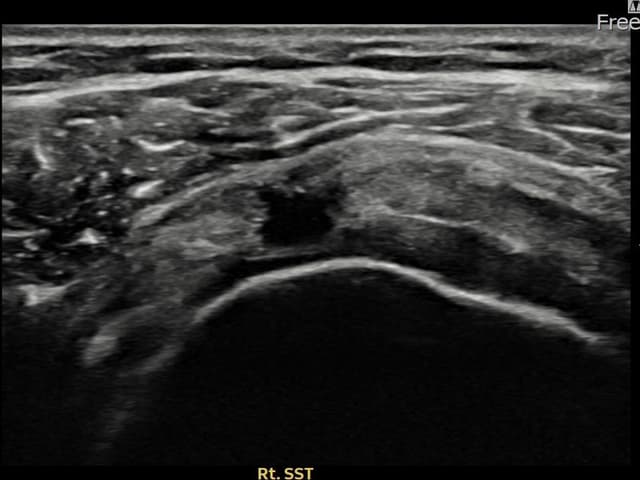

[촬영시기:22.09.19~22.12.09]

[어깨인대 축소봉합술] 우측 어깨 통증이 수개월간 지속되어 내원하셨습니다.